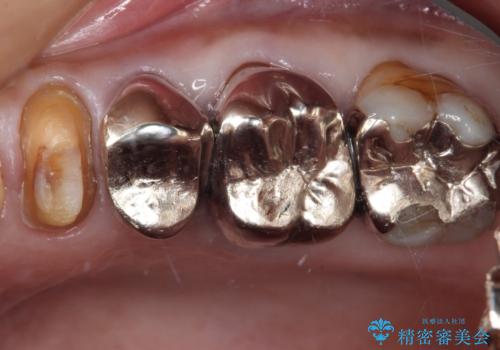

- 詰め物が欠けてしまい、虫歯かもしれないから診てほしいとのことで来院された患者様です。

精査の結果、詰め物の下に虫歯が大きく広がっているのがわかりました。

虫歯の範囲が大きく、部分的な詰め物では対応が難しいため、オールセラミッククラウンにて補綴することとしました。

また虫歯除去の際に、万一根管と交通してしまっても根管に感染を起こさないために、ラバーダム防湿をして虫歯除去しました。